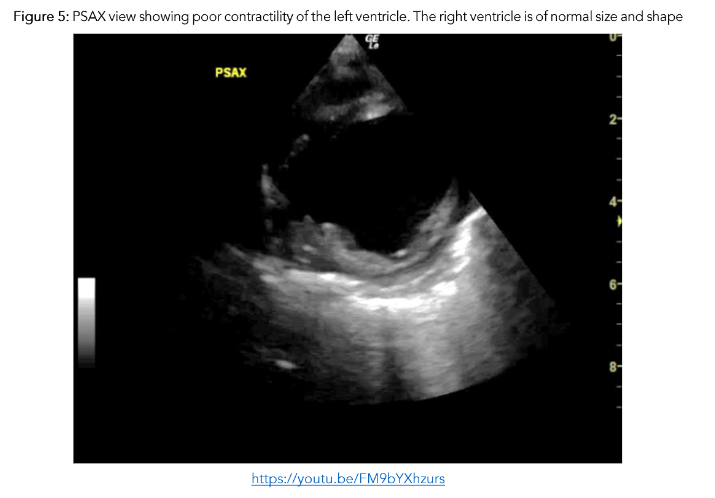

A previously well 9 month-old was brought to the ED by her mother with a recent history of bronchiolitis in the preceding 10 days. Although her initial upper respiratory symptoms had resolved, she now had reduced oral intake and urinary output. On assessment, the infant was tachypnoeic, tachycardic and had bilateral patchy infiltrates on CXR. As the baby was unwell with an undifferentiated shock, POCE was performed. It demonstrated very poor contractility of the left ventricle which contributed to a working diagnosis of myocarditis.

Early use of POCE demonstrated cardiovascular compromise and directed care appropriately to ensure judicious fluid management and avoidance of fluid overload, initiation of continuous cardiac monitoring to promptly alert to and manage arrhythmias, diuresis, and afterload reducing agents, with an option to escalate to inotropic support and mechanical ventilation if needed.